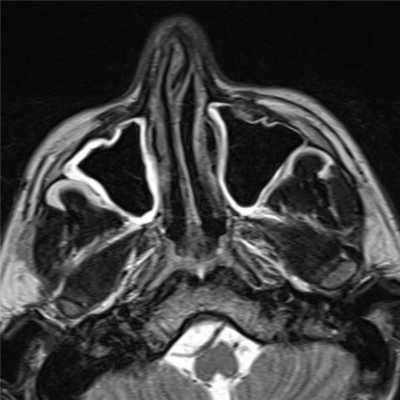

(Слева) При аксиальной МРТ Т2 ВИ у пациента с ХРС определяется снижение пневматизации левой верхнечелюстной пазухи. Содержимое в центре пазухи отчасти гипоинтенсивно из-за малого количества воды и большого количества белка. По периферии определяется воспаленная гиперинтенсивная слизистая оболочка.

• Т2ВИ:

о Слизистая оболочка обычно гиперинтенсивна

о Содержимое пазухи может быть гиперинтенсивным (↑ воды) или гипоинтенсивным (↓ воды, «сухое» содержимое)

о Утолщение стенок пазухи очевидно на MPT (Т2 ВИ)

(Слева) На аксиальной МРТ (Т2 ВИ) у пациента с ХРС определяется нарушение пневматиза-ции левой верхнечелюстной пазухи. Секрет в центре гипоинтенси-вен вследствие высокого содержания воды и малого количества белка. Воспаленная слизистая оболочка на периферии гиперинтенсивна.